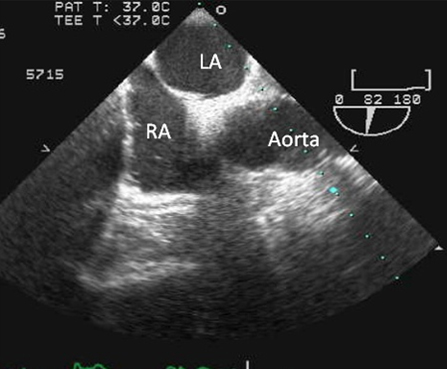

Performed in cases where a definitive diagnosis is sought; the transthoracic echo is either equivocal or negative; there is uncertainty as to whether the patient has atrial septal defect or PFO; and diagnosis is likely to alter management. [Figure caption and citation for the preceding image starts]: Transesophageal echo showing a 2D image of the interatrial septum with location of the PFOFrom the collection of Kul Aggarwal, MD [Citation ends].com.bmj.content.model.Caption@25b1fe2f[Figure caption and citation for the preceding image starts]: Transesophageal echo with intravenous injection of agitated saline showing contrast crossing through PFO into left atriumFrom the collection of Kul Aggarwal, MD [Citation ends].com.bmj.content.model.Caption@6d238800[Figure caption and citation for the preceding image starts]: Transesophageal echo with color flow Doppler showing presence of PFOFrom the collection of Kul Aggarwal, MD [Citation ends].com.bmj.content.model.Caption@2446563

visualization of defect, color flow at the interatrial septum and crossover of microbubbles from right atrium to left atrium after intravenous injection of agitated saline